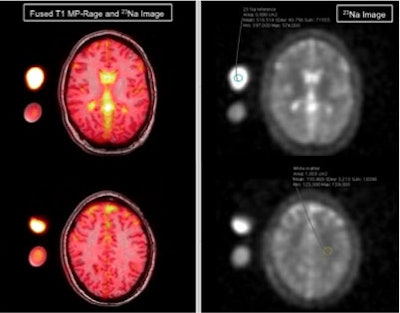

Dr. Melissa Meyer and colleagues from University Hospital Mannheim and Heidelberg University in Heidelberg, Germany, performed cerebral sodium MRI exams on healthy subjects and patients being clinically evaluated for migraine. They found that migraine patients had significantly higher sodium concentrations in the cerebrospinal fluid than those who did not have migraines.

To help improve the diagnosis and understanding of migraines, the German researchers sought to evaluate the use of cerebral sodium MRI. Sodium has been shown in prior research to play an important role in brain chemistry, according to the society.

They found that migraine patients had significantly higher sodium concentrations in the cerebrospinal fluid, according to the RSNA. No statistically significant differences were found between the two groups in terms of sodium concentration in the gray and white matter, brain stem, and cerebellum.